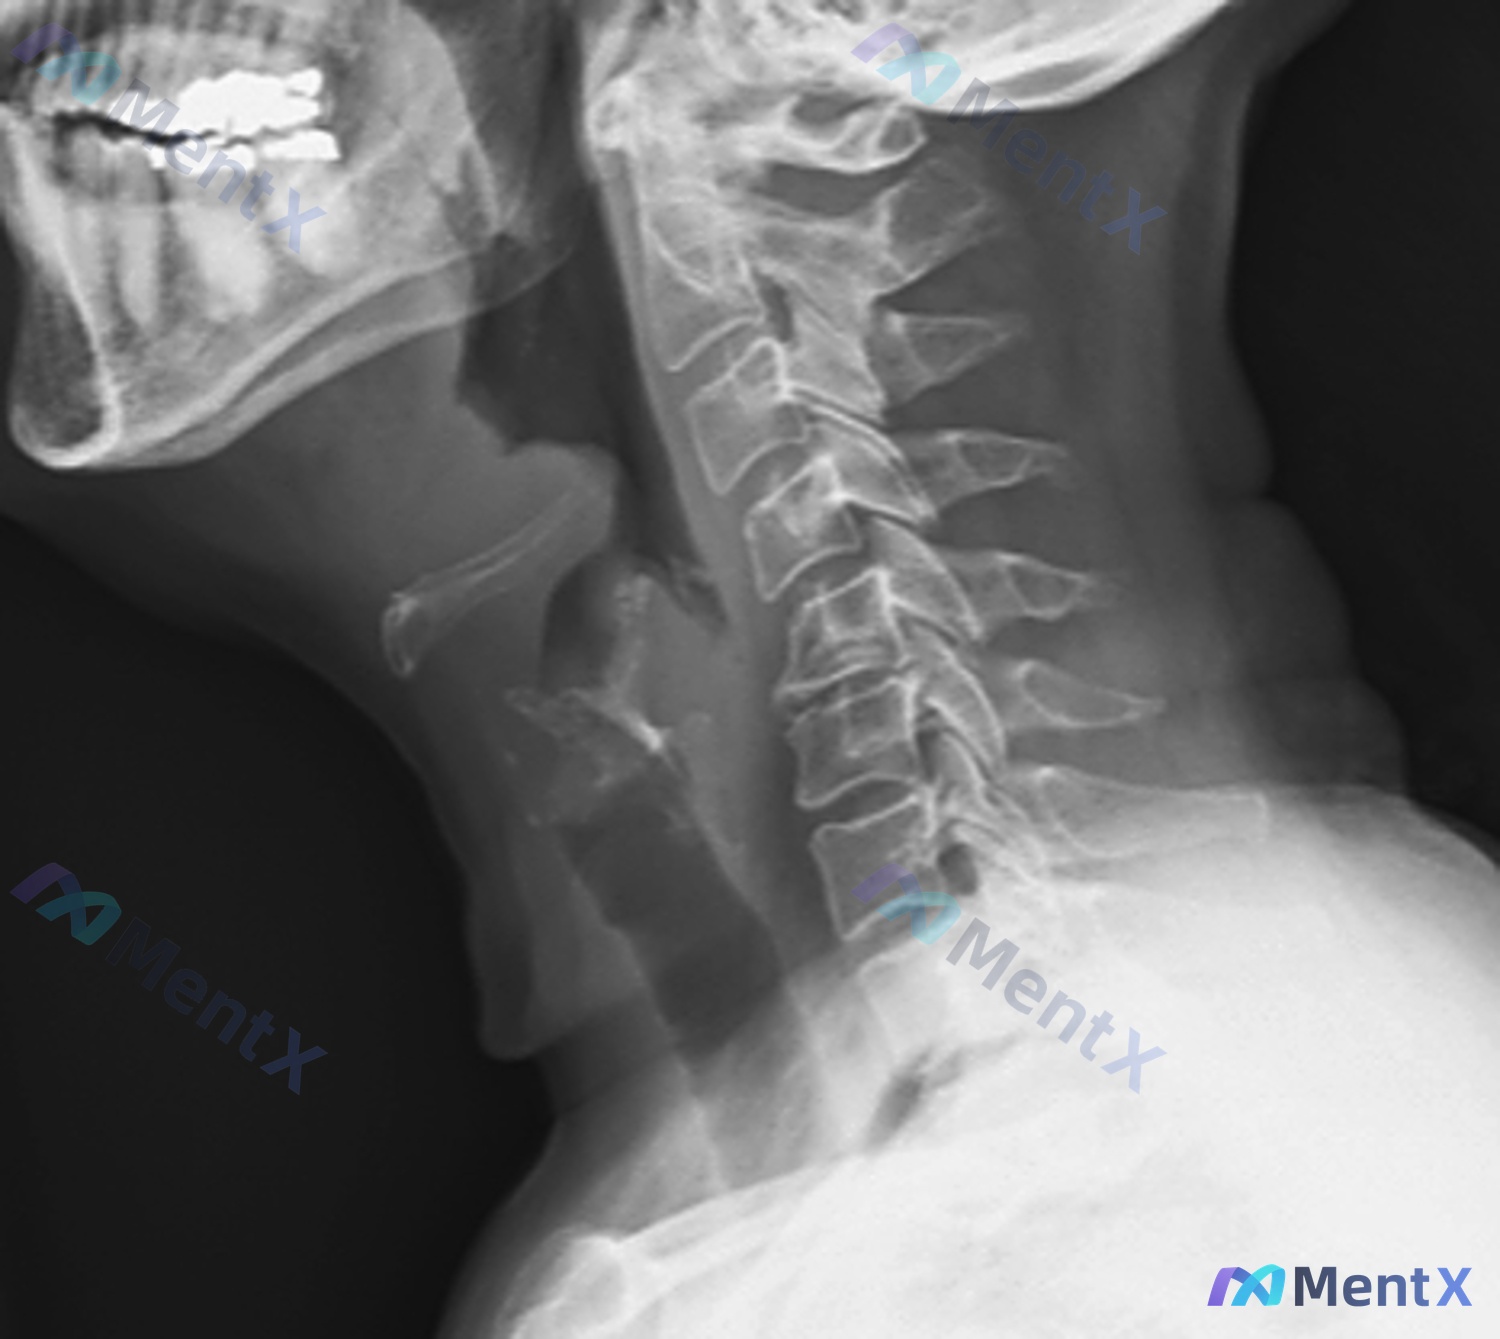

看到一个病例资料,整理了一下思路,感觉很容易踩坑,分享出来大家一起讨论。 病例基本情况 - 患者:65岁女性 - 主诉:喉咙疼痛、吞咽困难7天 - 影像:颈椎侧位X光片 先看影像给了什么线索 按照报告描述,我把关键点列出来: 1. 颈椎序列:生理前凸消失,变直了 2. 椎体骨质:密度减低(提示骨质疏...